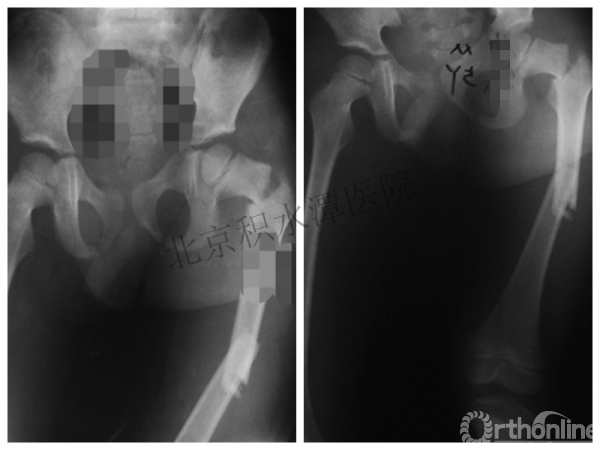

病例分享一

男孩 、5岁,初次骨折于2007年7月。

术后2年→再骨折→再次手术